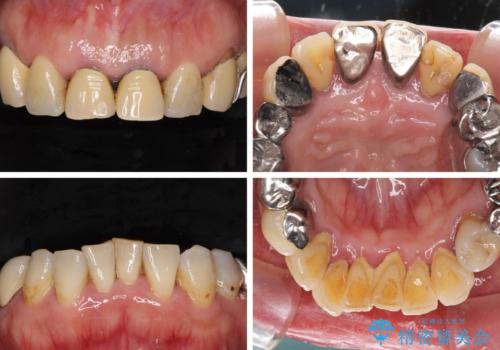

- 歯茎からの出血、入れ歯、歯の欠損、デコボコの前歯などを気にして来院された患者様です。

大の歯科治療嫌いとのことでしたが、今回の治療を契機にしっかりと治療を行いたいとのことでした。

まずは抜歯が必要な歯を抜歯した上で仮歯に置き換え、インプラント埋入や歯周外科処置、根管治療を行うこととしました。

歯肉の状態が落ち着いた後に下顎の矯正治療を行い、その後補綴治療を行うこととしました。

インプラントに対する恐怖心が強く、欠損補綴は極力ブリッジを採用し、インプラントの数は必要最小限としました。